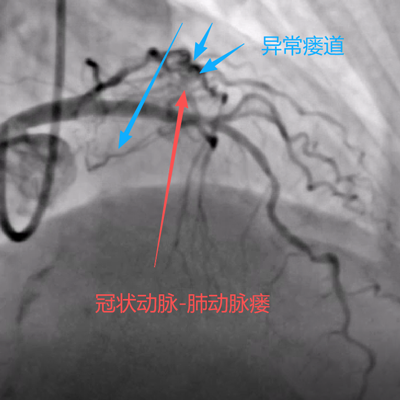

据悉,患者刘某近一年来反复出现胸闷、气短等症状,严重影响了日常生活。她来到县人民医院心血管内科就诊,经过详细检查,并完善冠状动脉造影检查,确诊其患有“冠状动脉-肺动脉瘘”。(如下图)

手术当日,在数字减影血管造影(DSA)设备的精确引导下,手术团队通过患者手腕部仅有米粒大小的穿刺点,将一根细如发丝的微导管,犹如“穿针引线”般精准送达深藏在心脏的异常瘘管内。随后,通过导管将栓塞物质置于瘘管的关键部位,成功实现了对异常通道的“精准封堵”。术后即刻造影显示,异常血流分流完全消失,被“盗走”的血液重新回到了正常的冠脉轨道,手术取得圆满成功。(如下图)